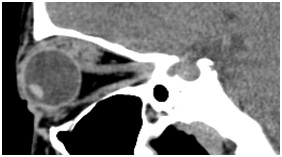

鼻窦(病例-异物):

眼眶(病例-眼上静脉扩张)